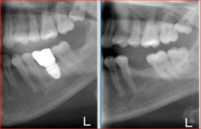

This patient came to see Dr. Andrews in our Boston Dental Practice with the desire to replace her missing lower left molar (#19). Since the extraction was done more than a year prior to the visit, more than 50% of the bone volume was lost. Being the second biggest tooth in the mouth, a lower molar requires a strong foundation to be built on.

Studies confirmed, that for long-term success, an implant diameter for such case should be no less than 5 mm. With only 3 mm width of the bone available here, no implant can be placed without a bone graft. The classic (old) treatment planning dictates the two-stage approach. The bone graft (ridge augmentation) is done first. After 4-5 months, when the bony ridge is wide enough (10-12 mm), an implant is placed. Then another 5-6 months are required for the implant to integrate with the bone. Add another month to make a crown. Thus, the total treatment time is 10-12 months.

Using modern, advanced surgical techniques, combined with PRF protocol, Dr. Andrews was able to combine bone graft with the simultaneous implant placement. He augmented the bone ridge wide enough to place 7 mm implant diameter. That is 200% more implant-to-bone surface area compared to a 5 mm one. Such a strong foundation should be able to support the implant crown for the entire patient’s life. This case took Dr. Andrews 5 months to complete, with only one surgery.